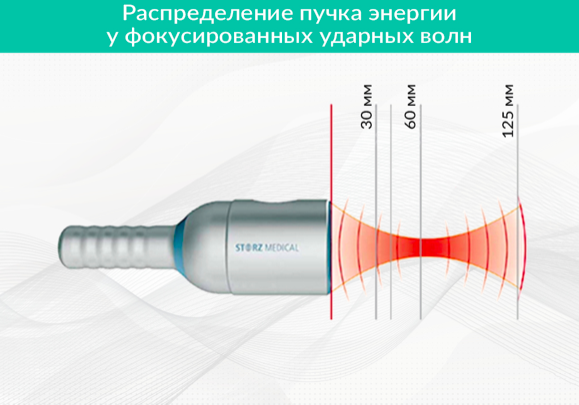

Фокусированная ударная волна проникает в ткань на большую глубину – до 12 см, при этом фокусное пятно может располагаться на максимальной глубине до 6 см, а радиальная не более 2-3 см, при этом терапевтически значимая энергия располагается обычно в первом сантиметре ткани.

Фокусированная ударная волна названа так, потому что фронты ее фокусируются в определенной области - фокусном пятне, имеющем высокую плотность энергии на единицу площади внутри пятна и относительно низкую плотность энергии областей вне его (Рисунок 1).

Рисунок 1. Фокусированная ударная волна

Фокусное пятно формируется с помощью специальных систем фокусировки аппаратов УВТ и имеет у наиболее распространенных аппаратов фокусное расстояние от нескольких миллиметров до 6 см. Фокусное расстояние – это расстояние от излучателя (аппликатора), прикладываемого к телу и используемого для проведения ударной волны внутрь тканей, до центра фокусного пятна. Фокусное расстояние может меняться с помощью насадок на аппликатор разной толщины, служащих своеобразными прокладками между излучателем и телом человека (Рисунок 2).

Рисунок 2. Насадки, позволяющие изменять расстояние до фокусного пятна

Фронт фокусированной волны характеризуется большой крутизной с почти мгновенным нарастанием давления за период, расположенный в наносекундном диапазоне. Величины положительного и отрицательного давления при прохождении фронта в десятки раз выше, чем у аппаратов, генерирующих радиальные волны давления.

Преимущества фокусированной волны:

- фокусное пятно имеет небольшие размеры, что позволяет с довольно высокой точностью наводить излучатель на место терапии;

- «фокусное расстояние» (расстояние от поверхности аппликатора, который прислоняется к телу, до фокусного пятна) можно изменять с помощью насадок, что позволяет воздействовать на ткани тела на разной глубине;

- фокусированная волна имеет высокую энергию и проникает в тело на глубину до 12 см, в отличие от радиальной, имеющей глубину проникновения 1-2 см;

- фокусированная волна помимо «тканевых эффектов» (уменьшение воспаления, прорастание капилляров, приток стволовых клеток и т.д.) вызывает эффект разрыхления тканей. Это часто является ключевым преимуществом (особенно при компрессии нервов, лечении триггерных точек, кальцинатов, болевых синдромах, где жесткость ткани играет важную роль) перед радиальной волной, вызывающей «только тканевые эффекты» в самых верхних слоях тканей.